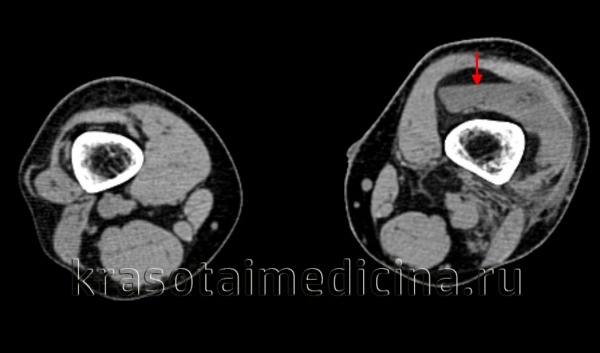

КТ коленных суставов. Уровень жидкости в супрапателлярной сумке слева у пациента с переломом мыщелков левой большеберцовой кости.

3. КТ при гемофилии:

• Важная для оценки перегородок и тонкого кортикального ободка псевдоопухоли

• При КТ с контрастированием можно определить границы и толщину стенки периферической капсулы

• Вариабельная КТ-плотность в центральной части, соответствует различными стадиям кровоизлияния